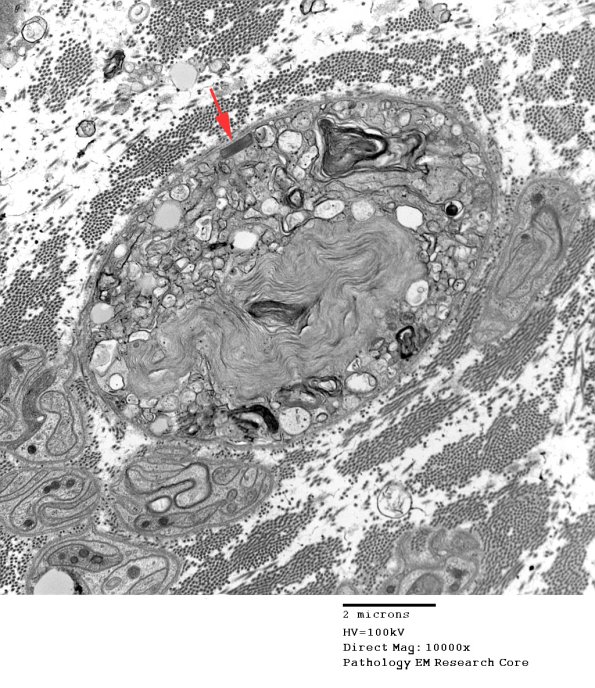

2E5,6 A pi granule preserves its periodicity which is narrower than myelin.